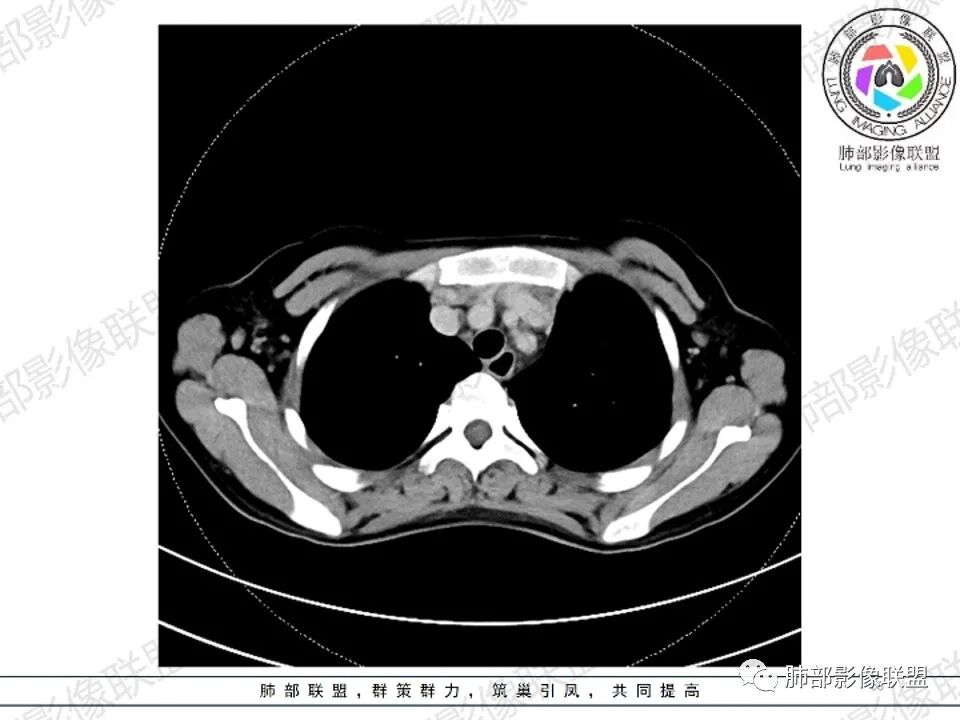

2.影像显示前纵隔不规则块状影,依势贴附心脏大血管旁,密度不均,边界不甚清楚,有结节融合感。

3.病灶轻度不均匀强化,可见血管穿行,散在液性低密度区。

双肺门未见肿大淋巴结。